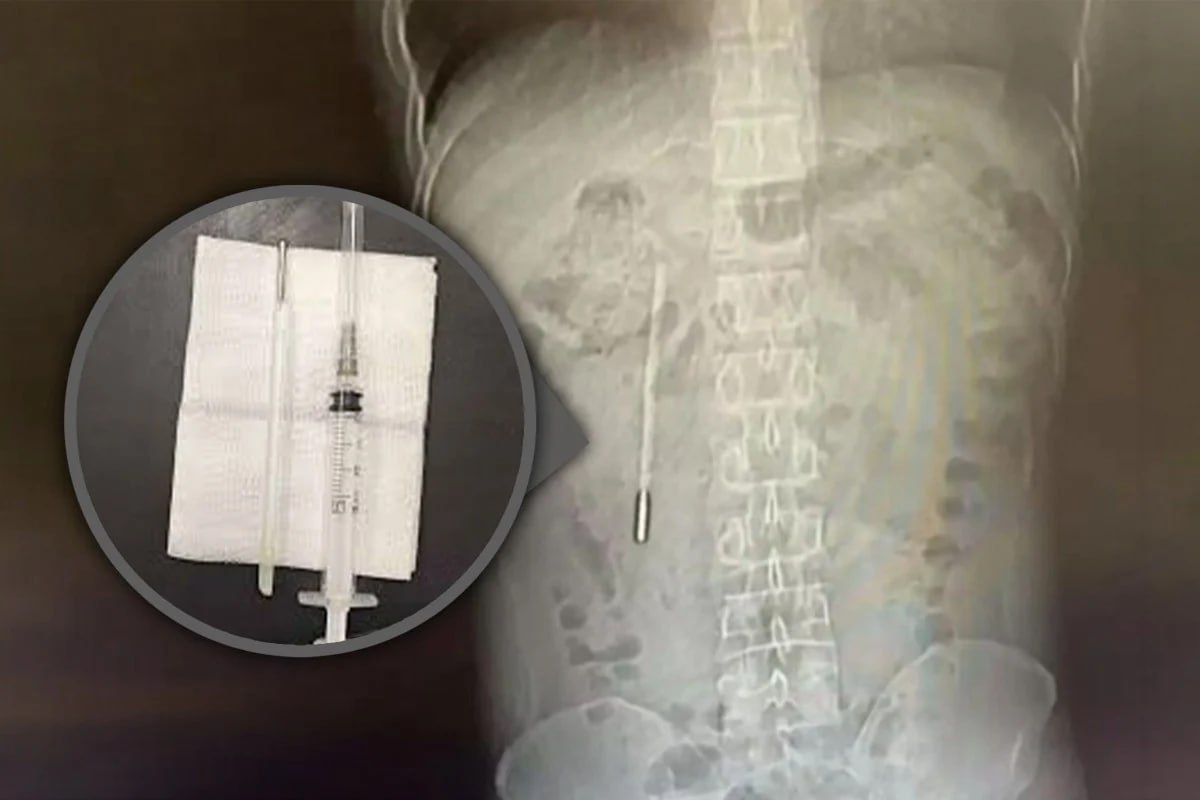

Έβγαλαν θερμόμετρο από Κινέζο που είχε καταπιεί πριν από 32 χρόνια!

Η συσκευή παρέμεινε άθικτη και λειτουργική!

Ένας 32χρονος άνδρας στην Κίνα ζήτησε ιατρική βοήθεια μετά από έντονο πόνο στο στομάχι — και οι γιατροί ανακάλυψαν ένα θερμόμετρο που είχε καταπιεί ως παιδί ήταν ακόμα μέσα του, — South China Morning Post.

Σύμφωνα με αναφορές, κατά λάθος κατάπιε τη συσκευή πριν από χρόνια, αλλά φοβόταν πολύ να το πει στους γονείς του και τελικά την ξέχασε.

Με την πάροδο του χρόνου, άρχισε να πιέζει τους εσωτερικούς ιστούς, δημιουργώντας κίνδυνο εσωτερικής αιμορραγίας.

Οι χειρουργοί αφαίρεσαν με επιτυχία το θερμόμετρο κατά τη διάρκεια μιας επέμβασης.

Η συσκευή παρέμεινε άθικτη, αν και οι ενδείξεις θερμοκρασίας της είχαν ξεθωριάσει.